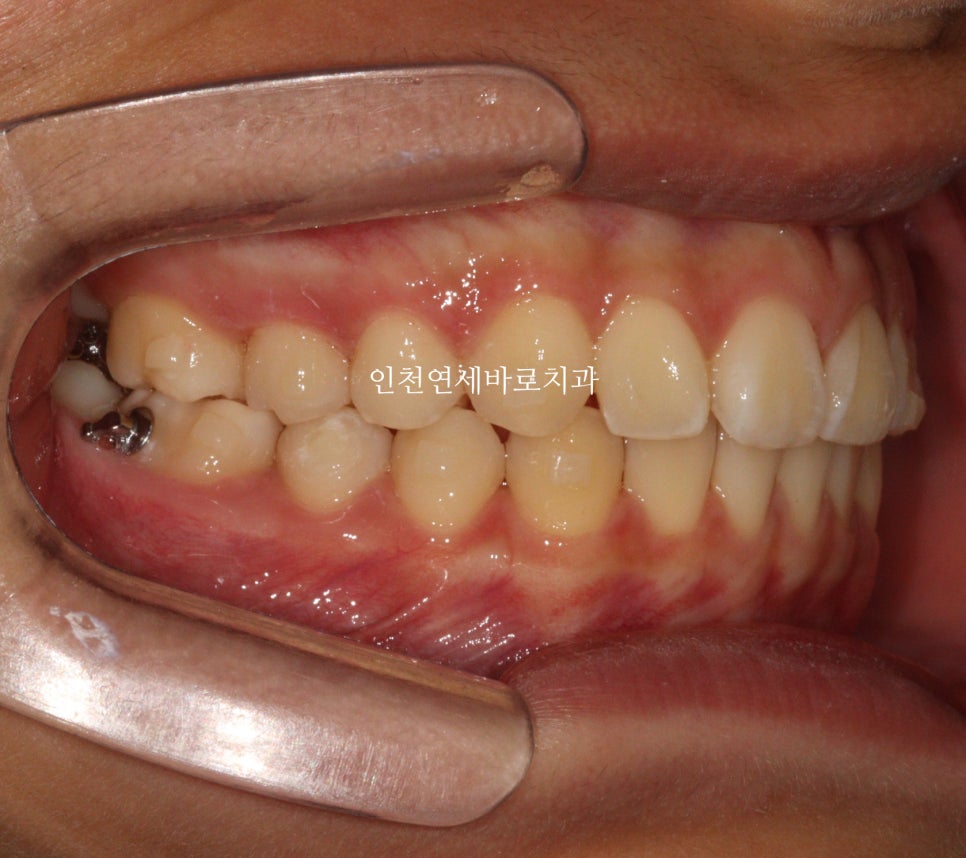

인비절라인 첫 단계를 시작했습니다.

중간 모습입니다.

공간을 살살 벌리니 위에 위치하고 있던 치아사 살살 내려옵니다.